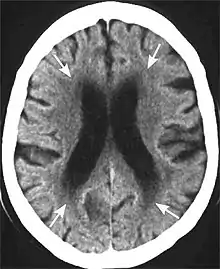

Axial T2 FLAIR sequence MR image of a middle-aged man with leukoaraiosis.

Leukoaraiosis is a particular abnormal change in appearance of white matter near the lateral ventricles. It is often seen in aged individuals, but sometimes in young adults.[1][2] On MRI, leukoaraiosis changes appear as white matter hyperintensities (WMHs) in T2 FLAIR images.[3][4] On CT scans, leukoaraiosis appears as hypodense periventricular white-matter lesions.[5]

These white matter changes are also commonly referred to as periventricular white matter disease, or white matter hyperintensities (WMH), due to their bright white appearance on T2 MRI scans. Many patients can have leukoaraiosis without any associated clinical abnormality. However, underlying vascular mechanisms are suspected to be the cause of the imaging findings. Hypertension, smoking, diabetes,[3] hyperhomocysteinemia, and heart diseases are all risk factors for leukoaraiosis.